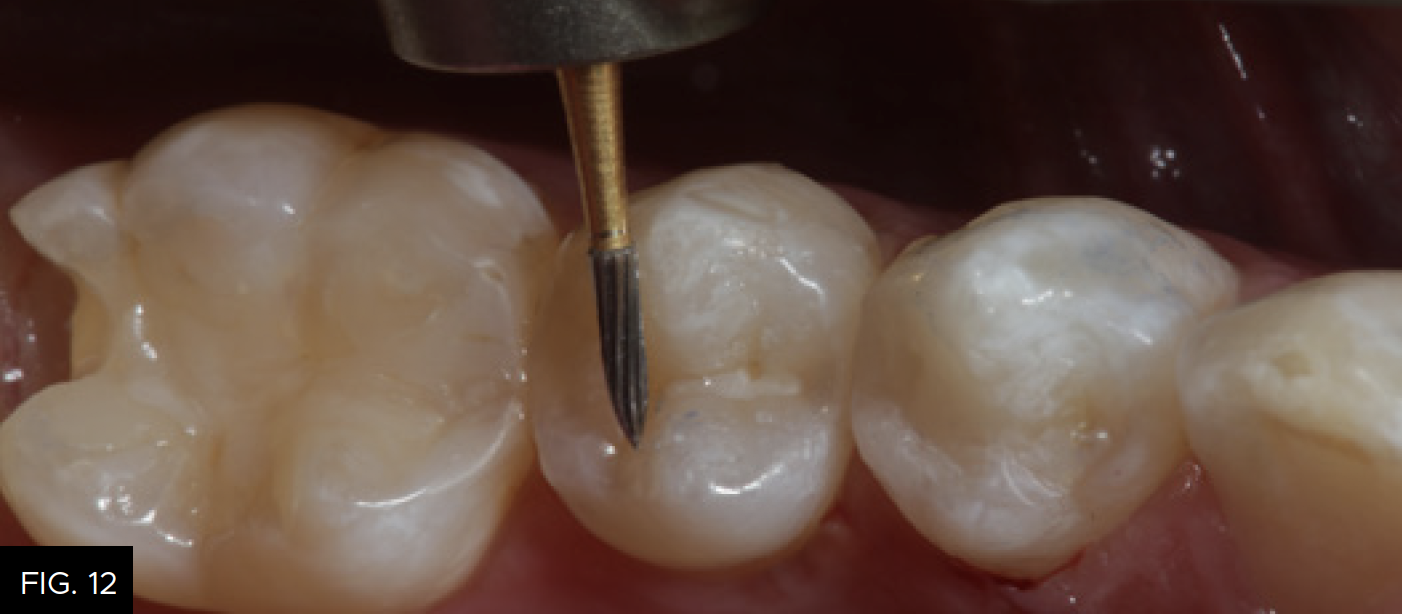

Each increment of composite material should be no more than 2 millimeters thick. The buccal increment is placed into the facial portion of the preparation, including the facial portion of the marginal ridge. The cuspal projections are sculpted and the depressions between are created using the Flexithin Mini 4. A #2 Flat Keystone brush (Patterson Dental) is lightly dipped in resin (ResinBlendLV, Clinician’s Choice), dried thoroughly with a 2X2 sponge and used to feather the material toward the margins while smoothing the surface of the composite. After fully light-curing, occlusion is checked with articulation paper and adjusted, as needed using a thin 20-fluted carbide composite finishing bur (SS White). (FIG. 12)

A 20-fluted carbide composite finishing bur (#9904, SS White) is used to adjust the occlusion prior to polishing the restoration.